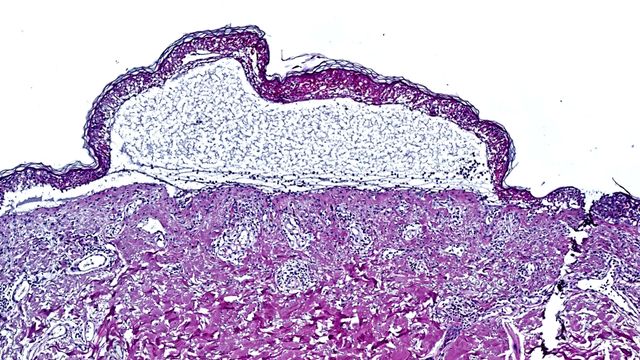

Targeting the JAK/STAT Pathway in Toxic Epidermal Necrolysis

Researchers have made a groundbreaking discovery that saves the lives of patients suffering from toxic epidermal necrolysis. Using innovative spatial proteomics the team identified the inflammatory JAK/STAT pathway as the main driver of disease.